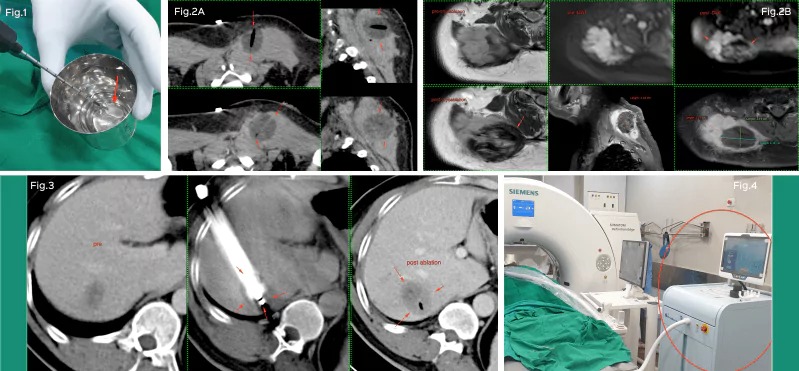

Explore innovative healthcare solutions with our advanced cryoablation treatment, designed to provide safe and effective medical outcomes. This minimally invasive procedure is used in various therapeutic applications, offering patients improved comfort and faster recovery times. At Picture This, we focus on delivering reliable and professional healthcare services with the highest standards of care. Whether you’re seeking information or considering this treatment option, our team ensures clarity and support at every step. Get in touch with Picture This today to learn more or discuss your specific requirements.